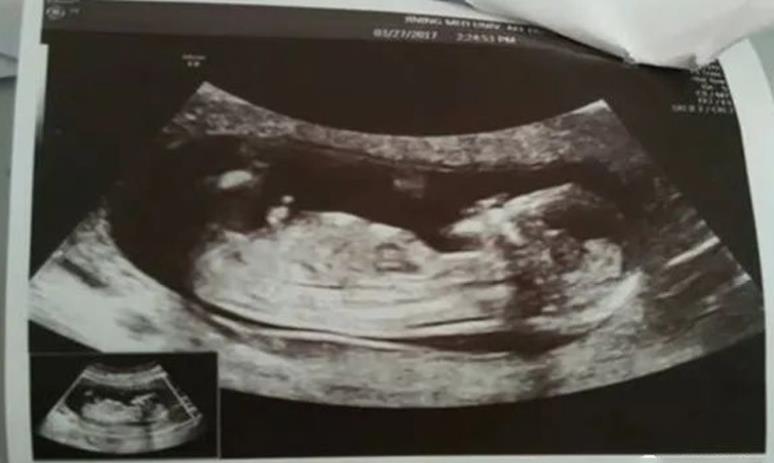

2、试管婴儿进行的步骤 1、控制性超排卵 2、监测卵泡 3、取卵 4、取精 5、体外受精 6、胚胎体外培养 7、胚胎移植 8、胚胎移植后补充黄体酮 9、胚胎移植后第14天验晨尿确定是否妊娠 10、妊娠后14天,B超检查胎儿数及胚胎着床部位

4、监测卵泡: 为评价卵巢刺激效果与决定取卵时间,须利用阴道B超来监测卵泡大小,并配合抽血检查E2值 (雌激素),调整用药量。当二至三个以上的卵泡直径大于1.8cm,且1.4cm以上的卵泡数与E2值相当,便可注射人绒毛促性腺激素(hCG),促使卵泡成熟。在注射hCG后34~36小时取卵。

5、取卵: 最常用的取卵方式是在的局部麻醉下,经阴道B超引导,将取卵针穿过阴道穹窿,直达卵巢吸取卵子,并立即在显微镜下将卵子移到含胚胎培养液的培养皿中,置37 C的培养箱中培养。

8、胚胎移植: 受精卵在体外培养48~72小时可发育到8~16细胞期胚胎。此时依据患者的年龄、曾经怀孕与否及胚胎的质量,决定移植胚胎的数目,多余的胚胎可冷冻保存。胚胎移植一般不需麻醉。目前多在受精后2~3天移植胚胎,我所采用的是受精后3~5天胚胎移植。推迟胚胎移植的时间,对体外培养的条件要求就越高,但推迟移植时间更符合妊娠生理,同时也可通过自然筛选淘汰劣质胚胎,可提高妊娠率,降低多胎率。